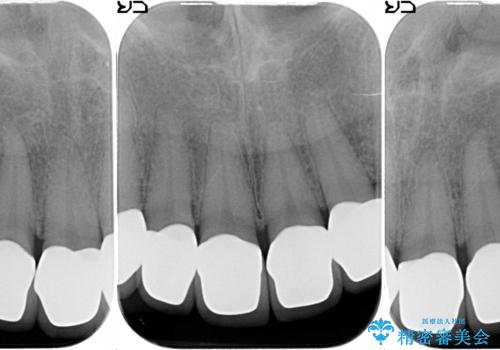

- 上下顎前歯部の見た目が気になるといらっしゃった方の症例です。

上顎は左4番から右4番までの8歯、下顎は左3番から右3番までの6歯、計14歯をオールセラミッククラウンにより補綴しました。

今回用いたオールセラミッククラウンはジルコニアフレームという白い素材の上にセラミックを盛っているため、審美性が非常に高いのが特徴です。

また、ジルコニアは人工ダイヤモンドの材料にも使われているほど高い強度を持っており、そのためオールセラミッククラウンは審美性だけでなく、奥歯やブリッジの補綴も可能とするクラウンです。